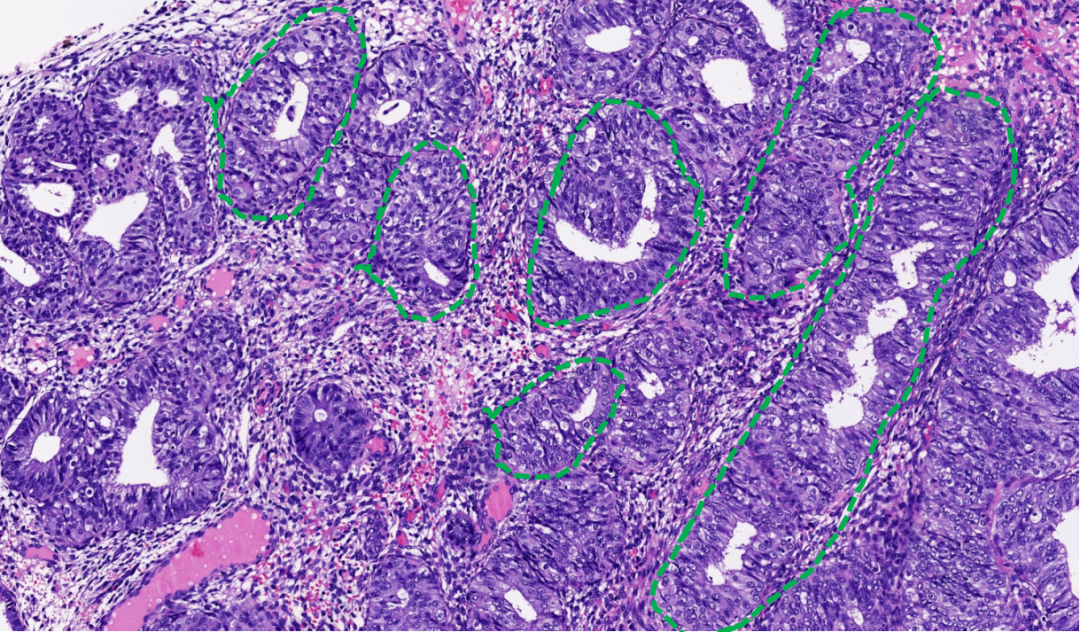

子宫内膜息肉和AH/EIN都可能出现腺体拥挤、分支和囊状扩张。但子宫内膜息肉通常表现为局灶性改变,腺体结构虽可不规则,但拥挤程度相对较轻,腺体走向常与表面上皮平行。其间质通常是纤维性的,并可见扩张的厚壁血管。息肉中拥挤腺体的细胞学特征通常与背景非拥挤腺体相似。只有当拥挤腺体出现明显的细胞核增大、核复层化和极性丧失等非典型性改变时,才应考虑AH/EIN的诊断。

图示:子宫内膜息肉,腺体拥挤、分支、形态不规则,走向与表面平行(绿色虚线),伴纤维性间质(黄色箭头)。